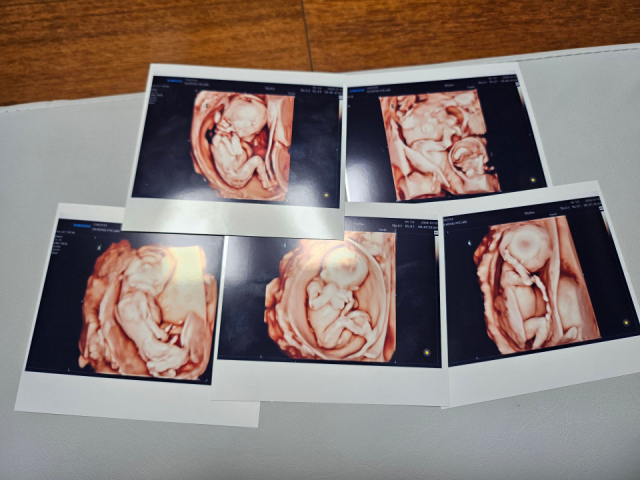

다섯쌍둥이의 초음파 사진. 연합뉴스 다섯쌍둥이의 초음파 사진. 연합뉴스

동두천시에 거주하는 이들 부부는 지난 20일 서울 성모병원에서 자연임신으로 다섯쌍둥이를 건강하게 출산했다. 남자아이 3명과 여자아이 2명이다.

이들 부부는 산부인과에서 치료와 임신 준비를 위해 배란유도제를 맞은 후 바로 다섯쌍둥이가 생겼다. 다섯쌍둥이가 자연임신으로 생겨 건강하게 태어난 것은 국내에서 최초인 것으로 알려졌다.